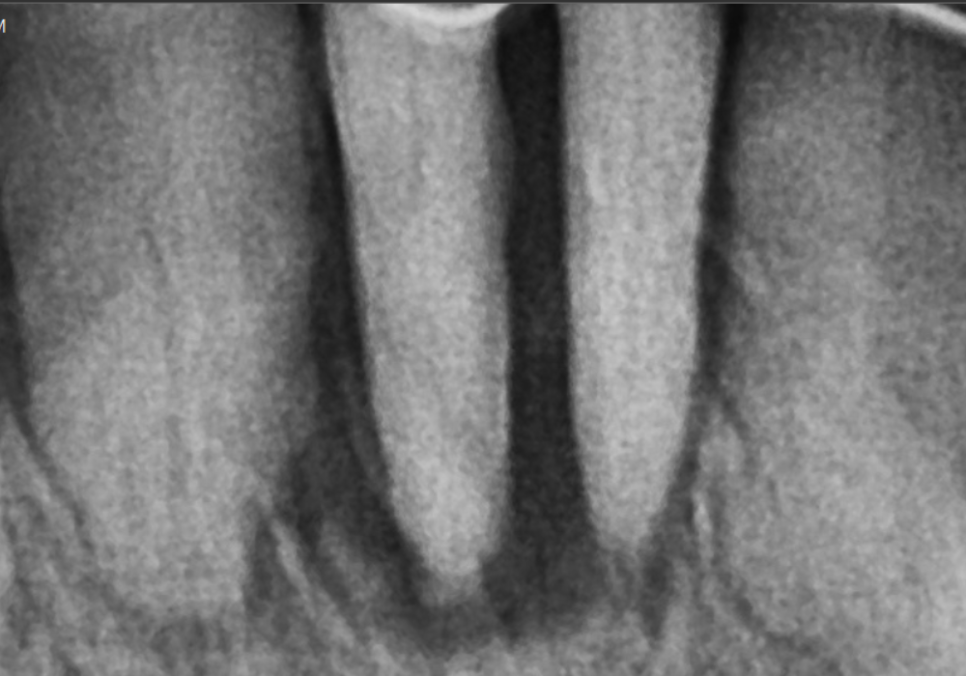

오른쪽 아래 맨 끝 어금니(#47) 부위를 보시면

뿌리 끝부분이 까맣게 보이죠.

뿌리끝에 염증이 생겨서 이 염증으로 인해

뼈가 녹아 까맣게 보이는데요~

잇몸뼈는 밀도가 높을수록

하얗게 나타나고,

염증으로 인해 뼈가 녹아

밀도가 낮아지면 이렇게 까맣게 보이게 됩니다.